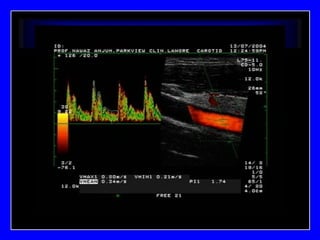

Carotid Artery

SYSTOLIC-MEAN=PI